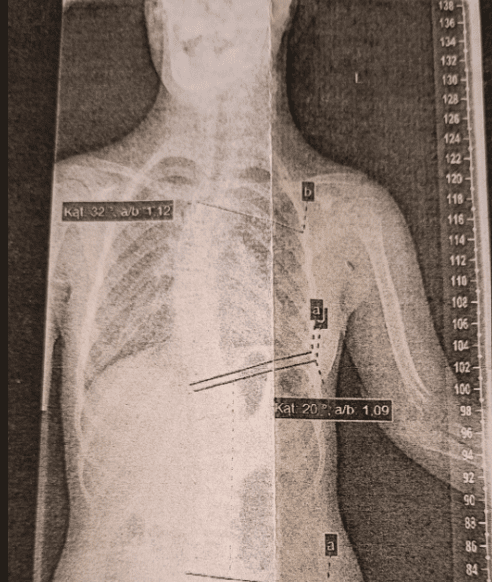

Ania ma 15 lat.

Urodziła się z Zespołem Downa i już w pierwszym roku życia przeszła skomplikowana operację serca, której skutkiem jest stopniowo rosnąca skolioza / w tej chwili 40 stopni/. Potrzebuje intensywnego turnusu rehabilitacyjnego, który uchroniłby ją przed operacją kręgosłupa / dwa tygodnie po 4-5 godzin/.